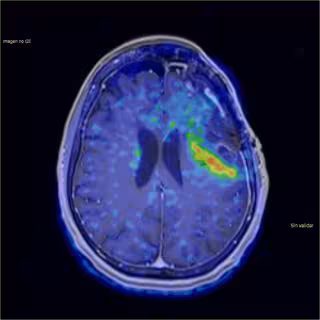

Una investigación europea en la que han participado expertos de la Universidad Politécnica de Madrid ha logrado utilizar imágenes hiperespectrales en la cirugía de tumores cerebrales consiguiendo así resultados mucho más precisos en las operaciones, concretamente, proporcionan información mucho más precisa de los márgenes del tumor que la que se obtendría a simple vista o con la ayuda de un microscopio.

HELiCoiD, nombre que recibe el proyecto internacional, utiliza las imágenes obtenidas de un par de cámaras hiperespectrales durante la cirugía cerebral para ayudar al neurocirujano a que realice una mejor resección del tumor, lo que reduce la posibilidad de complicaciones posteriores a la intervención y mejora el pronóstico del paciente.

Gracias a las posibilidades de la imagen hiperespectral los cirujanos pueden diferenciar mejor el tejido sano del canceroso y si el procesamiento se realiza a la velocidad adecuada, puede asistir al neurocirujano, en tiempo real, en la toma de decisiones durante las operaciones. Algo fundamental ya que "la cantidad de tejido extraído en la resección de este tipo de tumores tiene un efecto decisivo sobre la calidad de vida posterior del paciente", asegura Rubén Salvador, otro de los investigadores participante en HELiCoiD.